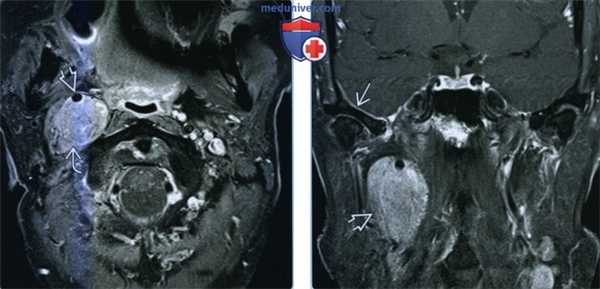

(Слева) КТ с контрастированием, аксиальный срез: у беременной женщины 26 лет с внезапной потерей зрения определяется накапливающее контраст супраселлярное объемное образование.

(Справа) Исходя из опасения о наличии геморрагического новообразования гипофиза была проведена МРТ. На корональных Т2-ВИ определяются нормальный гипофиз в сочетании с расположенным над ним гиперинтенсивным объемным образованием ( четкими контурами, которое развивается из диафрагмы седла. Отчетливо наблюдается отсутствие связи образования с железой. При хирургическом лечении была диагностирована классическая менингиома диафрагмы седла (grade I). (Слева) КТ с контрастированием, аксиальный срез: у пациента с первичной менингиомой оболочки зрительного нерва отмечается интенсивное контрастирование левого зрительного нерва. Данные изменения описаны в литературе как симптом «трамвайной линии».

(Справа) МРТ, постконтрастное Т1-ВИ, аксиальный срез: у другого пациента с вторичной менингиомой оболочки зрительного нерва определяется менингиома, растущая из области клиновидного гребня вокруг переднего наклоненного отростка, сужающая пещеристый сегмент внутренней сонной артерии, распространяющаяся через зрительный канал и инфильтрирующая оболочку зрительного нерва.

(Слева) МРТ, Т2-ВИ, аксиальный срез: в правом мостомозжечковом углу (ММУ) визуализируется объемное образование с четкими контурами, распространяющееся в правый внутренний слуховой проход.

(Справа) МРТ, постконтрастное Т1-ВИ, аксиальный срез: отмечается интенсивное и однородное контрастное усиление менингиомы в ММУ. (Слева) МРТ, Т2-ВИ, корональный срез: в области левой обонятельной луковицы определяется объемное образование изоинтенсивного по отношению к коре головного мозга сигнала с перифокальным отеком.

(Справа) МРТ, постконтрастное Т1 -ВИ, аксиальный срез: интенсивное и однородное контрастное усиление объемного образования, представляющего собой менингиому обонятельной борозды.

(Слева) МРТ, FLAIR, аксиальный срез: визуализируется дольчатое слегка гиперинтенсивное внутрижелудочковое объемное образование, растущее из клубка сосудистого сплетения. Обратите внимание на расширение височного рога левого бокового желудочка с перивентрикулярным интерстициальным скоплением мигрировавшей жидкости.

(Справа) МРТ, постконтрастное Т1-ВИ, аксиальный срез: определяется интенсивно и равномерно накапливающее контрастное вещество объемное образование (внутрижелудочковая менингиома). Около 1 % внутричерепных менингиом имеют внутрижелудочковую локализацию; здесь внутри сосудистого сплетения могут сохраняться остатки паутинной мозговой оболочки. (Слева) Бесконтрастная КТ, аксиальный срез: выраженные гиперостоз и кальцификация бляшечной менингиомы, распространяющейся вдоль внутренней компактной пластинки черепа слева.

(Справа) МРТ, Т1-ВИ, аксиальный срез: у этого же пациента определяется характерный гипоинтенсивный сигнал от зоны кальцификации/оссификации. (Слева) КТ с контрастированием, аксиальный срез: справа визуализируются несколько интенсивно накапливающих контраст в немозговых объемных образований с четкими контурами, которые были умеренно гиперденсны на бесконтрастных КТ-изображениях (не представлены).

(Справа) МРТ, постконтрастное Т1-ВИ, аксиальный срез: определяются интенсивно накапливающие контраст объемные образования. Множественные менингиомы чаще встречаются у женщин и пациентов с НФ2.